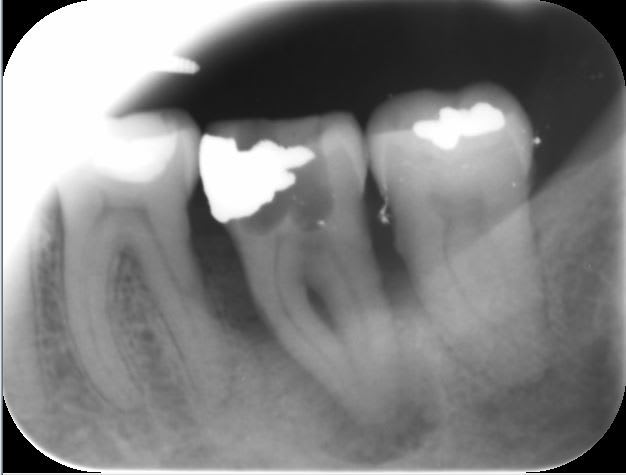

Lesion endo paro bdwn58 - Eugenol

J 0 obturation bof.. - Eugenol

J   3 mois  bonne surprise ya7tbg - Eugenol